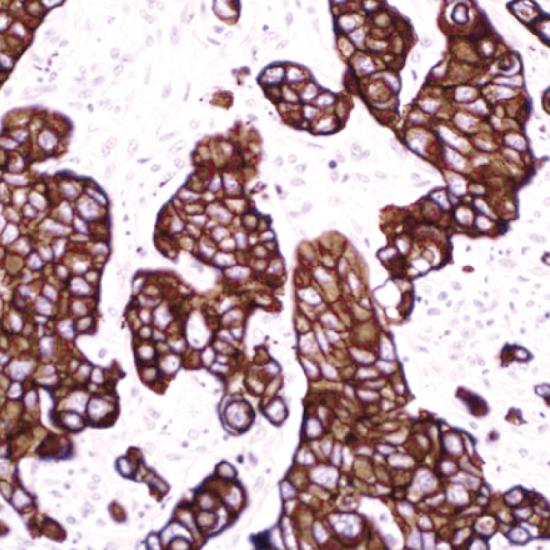

CK(CAM5.2)

CAM5.2是一種低分子量的細(xì)胞角蛋白,可作為單層上皮細(xì)胞的廣譜標(biāo)記物,定位于細(xì)胞漿。已發(fā)現(xiàn)CAM5.2對(duì)腺上皮和各種腺癌均呈強(qiáng)陽(yáng)性,腺上皮表達(dá)遠(yuǎn)強(qiáng)于復(fù)層鱗狀上皮,大量標(biāo)記結(jié)果顯示鱗狀上皮和尿路上皮不表達(dá)或低表達(dá)。CAM5.2廣泛用于鱗狀上皮和尿路上皮以外的上皮腫瘤標(biāo)記,是腺上皮和各種腺癌最常用的標(biāo)記物,它特異性強(qiáng),敏感性高,是目前認(rèn)為最理想的腺上皮腫瘤標(biāo)記物。